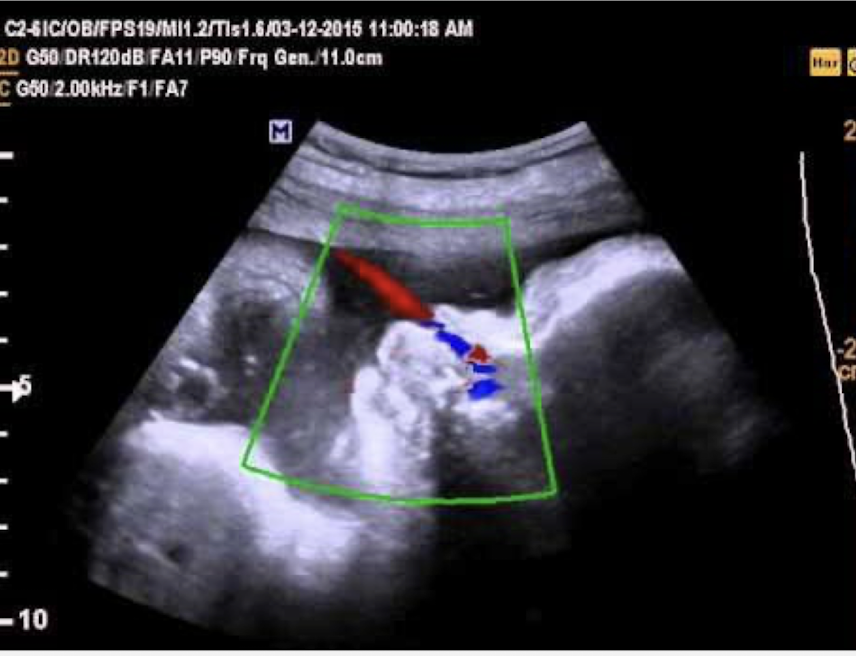

how can FB be documented?

color doppler and obtain a profile view